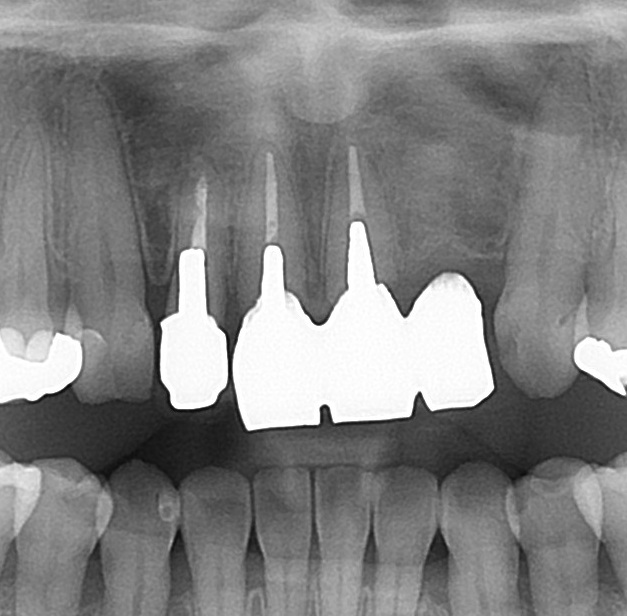

このような状態です。

前歯の4本がぶせ物で治療がされています。

こちらの4本ですね。

20年以上まえの治療で、歯が黄色く黄ばんで、歯の根元が黒くなっている箇所もあります。

こちらは「レジン前装冠」というかぶせ物で、表面の見える所はレジンというプラスティック樹脂で、内部から裏側には金属が使われています。